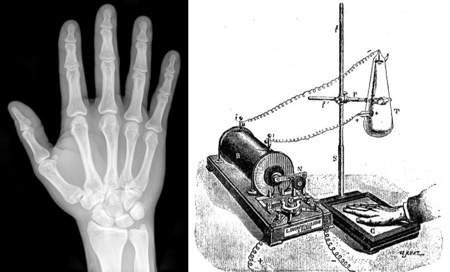

La luz visible puede atravesar algunas sustancias, como el agua o el vidrio, pero no nuestro cuerpo. Si queremos "ver" qué hay en su interior, tendremos que "iluminarlo" con otro tipo de ondas electromagnéticas: los Rayos X. Estos tienen una frecuencia de oscilación mucho más alta, que no es detectada por el ojo humano. Puede atravesar ciertos tejidos de nuestro cuerpo, como la piel y los músculos, pero no los huesos (tampoco los metales, y por eso nos hacen sacar cadenitas y relojes cuando nos sacan una radiografía).

Radiografía de una mano hecha en el Instituto Física de La Plata